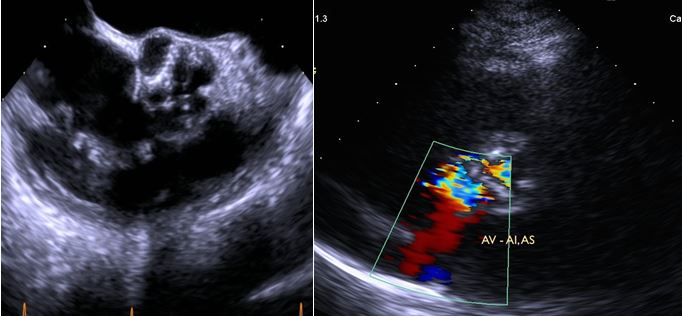

Fig. 3A: Mitral valve leaflet: thickened, redundant. Moderate central regurgitation. Subvalvular apparatus: nodular, thickened, fused.

Fig. 3B: Aortic Valve: thickened, nodular, calcified valve. Severe AS and mild AI.